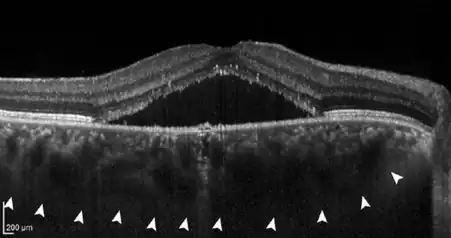

Central serous chorioretinopathy (pachychoroid stage II) with subretinal fluid (black triangle in the middle) and a markedly thickened, congested choroid (white arrowheads).

• If further damage to Bruch's membrane and the pigment epithelium causes fluid to accumulate under the retina, central serous chorioretinopathy (CCS) develops. In this stage, patients often have blurred vision and report a reduction in visual acuity with perception of a central "grey spot". In the majority of patients, spontaneous resolution of the subretinal fluid occurs within a few months, but recurs in up to 50% of cases. In some patients the fluid remains, making it a chronic disease; medical therapy or the application of various laser methods is possible.